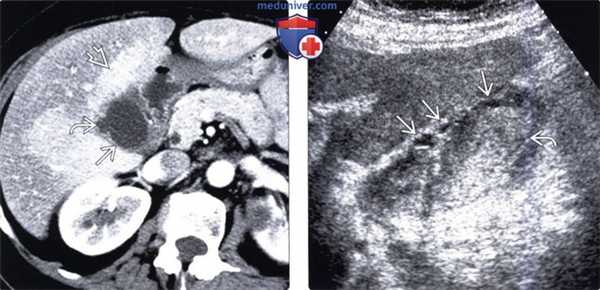

(Слева) На аксиальной КТ с контрастным усилением у мужчины 88 лет без какой-либо симптоматики, выполненной по поводу аневризмы аорты, определяется неравномерное утолщение стенки желчного пузыря с наличием в ней включений низкой плотности (случайная находка).

(Справа) На сонограмме у этого же пациента определяется утолщение стенки желчного пузыря с гипоэхогенными включениями в ней и наличием сладжа в просвете органа. При лапароскопической холецистэктомии подтвердился хронический ксантогранулематозный холецистит. При выраженном спаечном процессе и утолщении стенки в связи с хроническим воспалением часто возникает необходимость в открытой холецистэктомии.

УЗИ и КТ желчного пузыря. Ксантогранулематозный холецистит. Слева на УЗИ визуализируется (помечено стрелками) утолщение стенки желчного пузыря с интрамуральным включением и с камнем в просвете органа. Справа на КТ выявляется утолщение стенки с гиподенсными включениями.

Выше представлено КТ пациента 71 года с ксантогранулематозным холециститом. Постконтрастное КТ. Визуализируется утолщение стенки желчного пузыря с включениями, которые соответствуют абсцессу или фокусам воспаления.